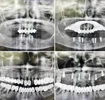

Implant tedavisi